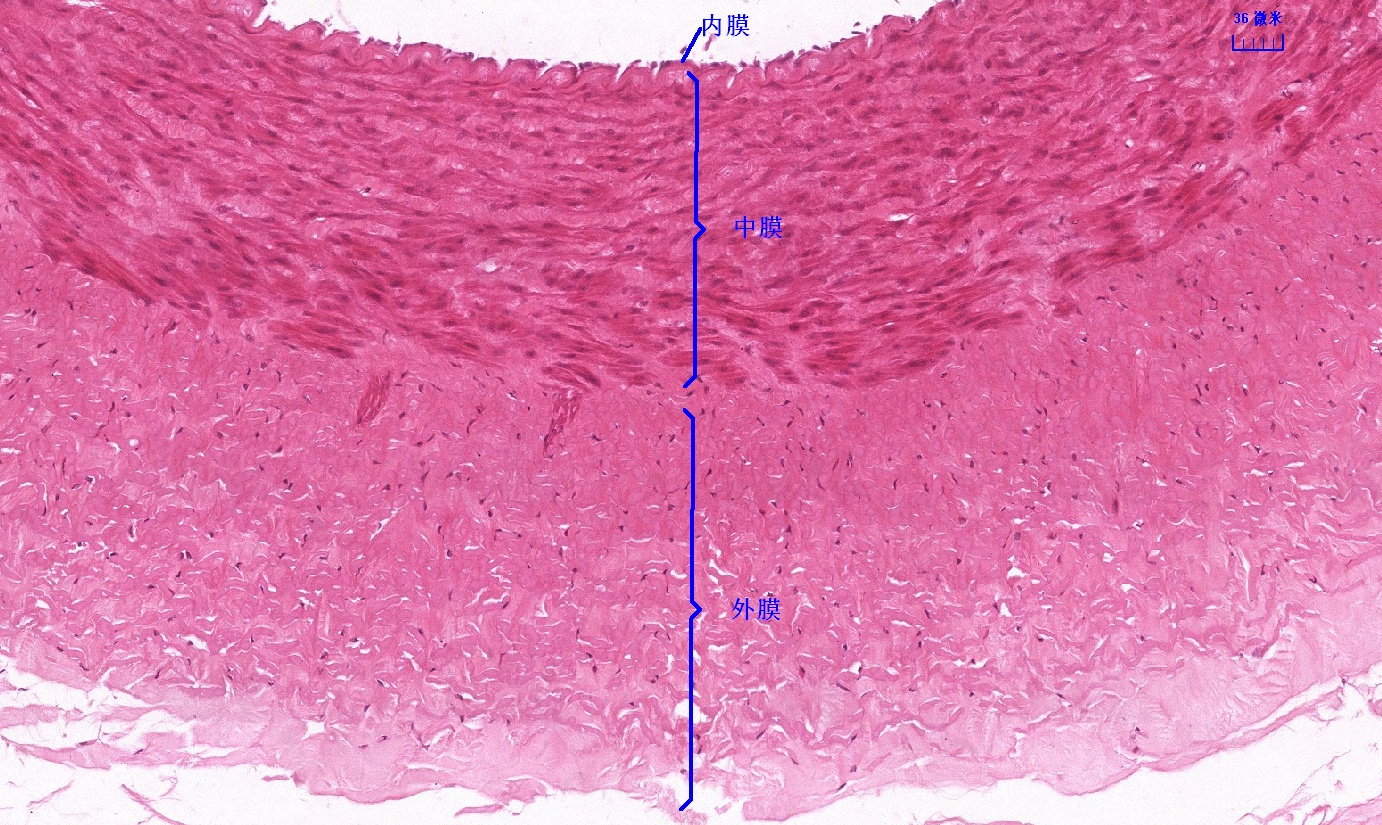

6.1 循环系统切片库